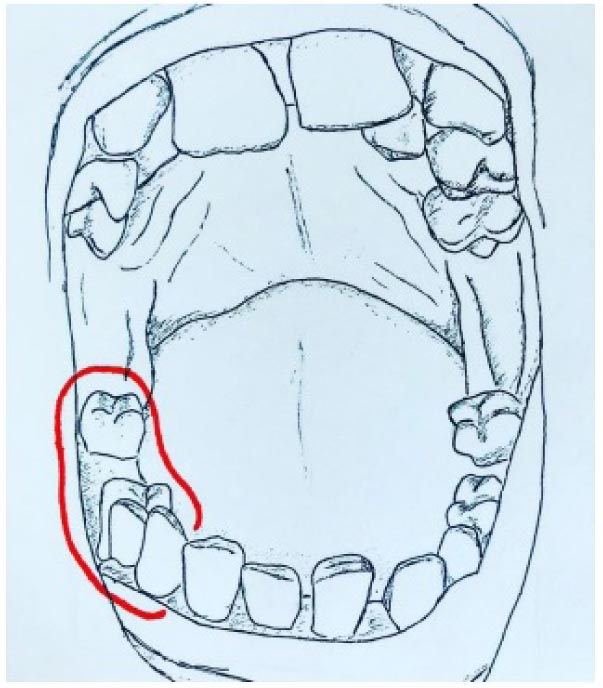

Vincenzo Ronsivalle, Federica Casella, Grazia Fichera, Orazio Bennici, Cristina Conforte and Antonino Lo Giudice